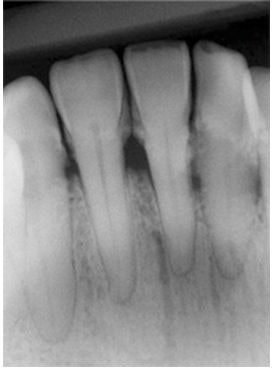

A similar type of evaluation can be done with periodontal disease using XDR software by Cyber Nedical Imaging.

On the left below is the initial radiograph, and on the right is the radiograph after enhancing the image.

![]() ![]() |